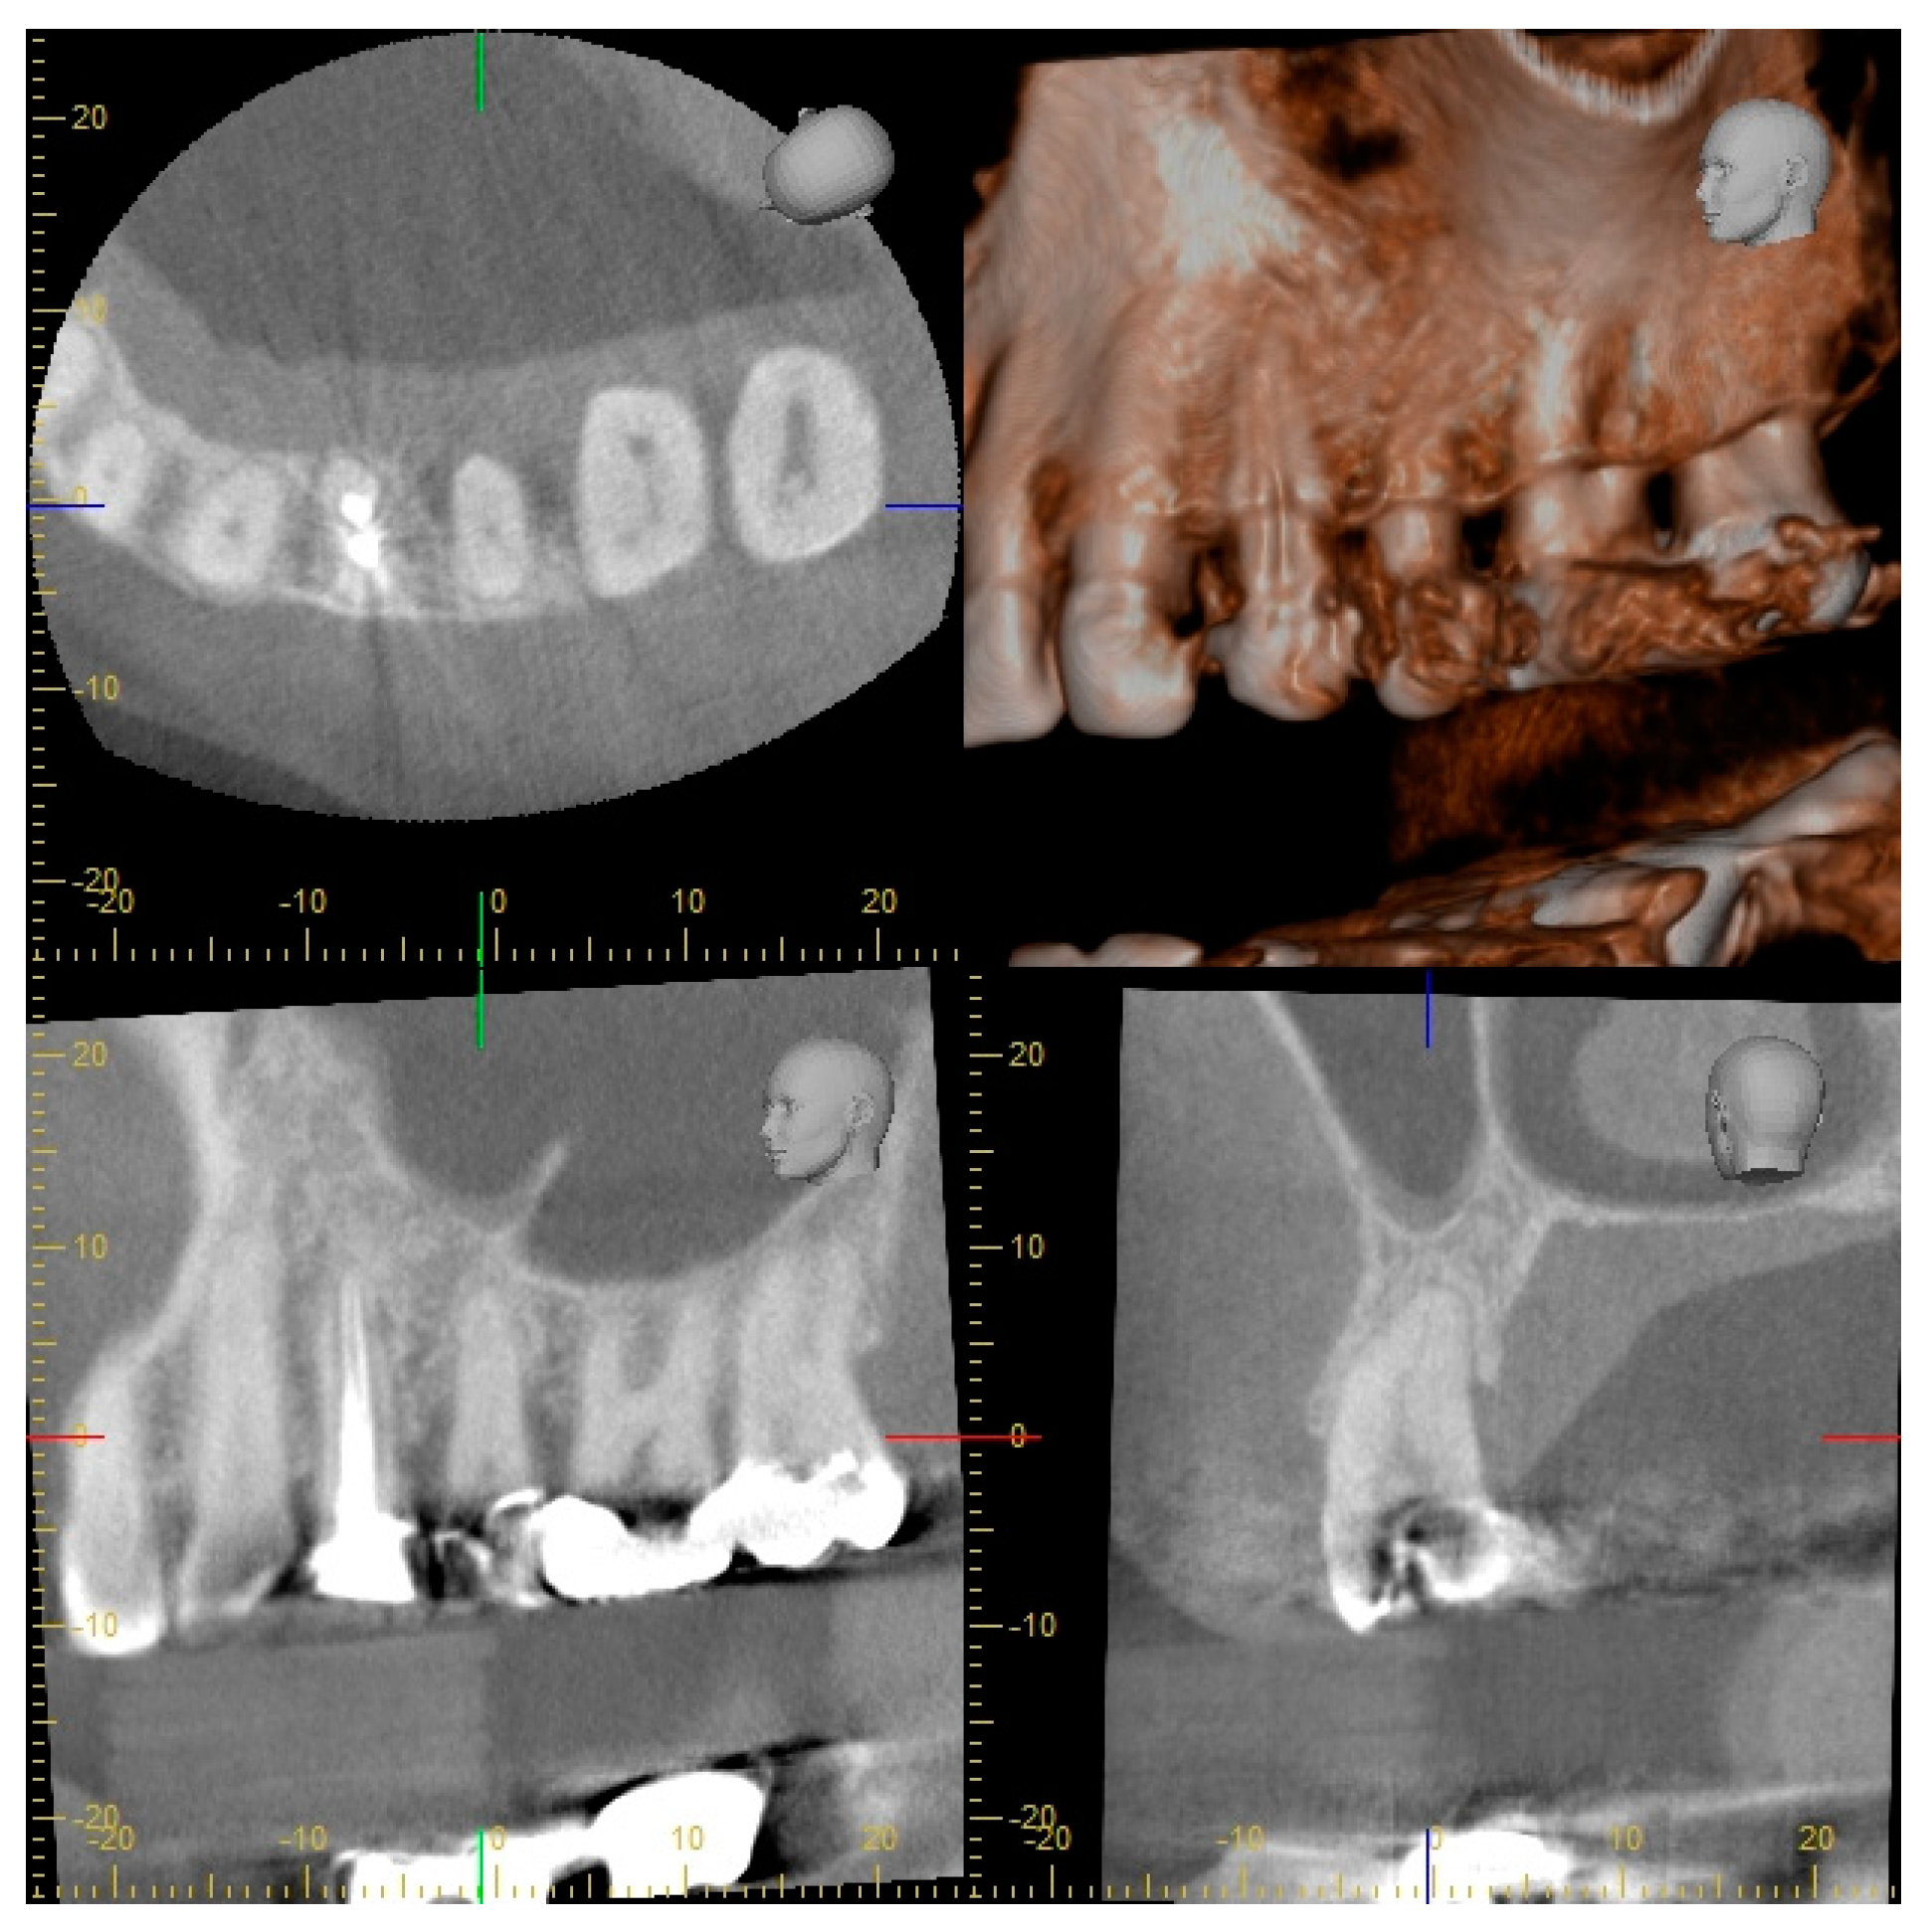

2.2. Radiographic Methods